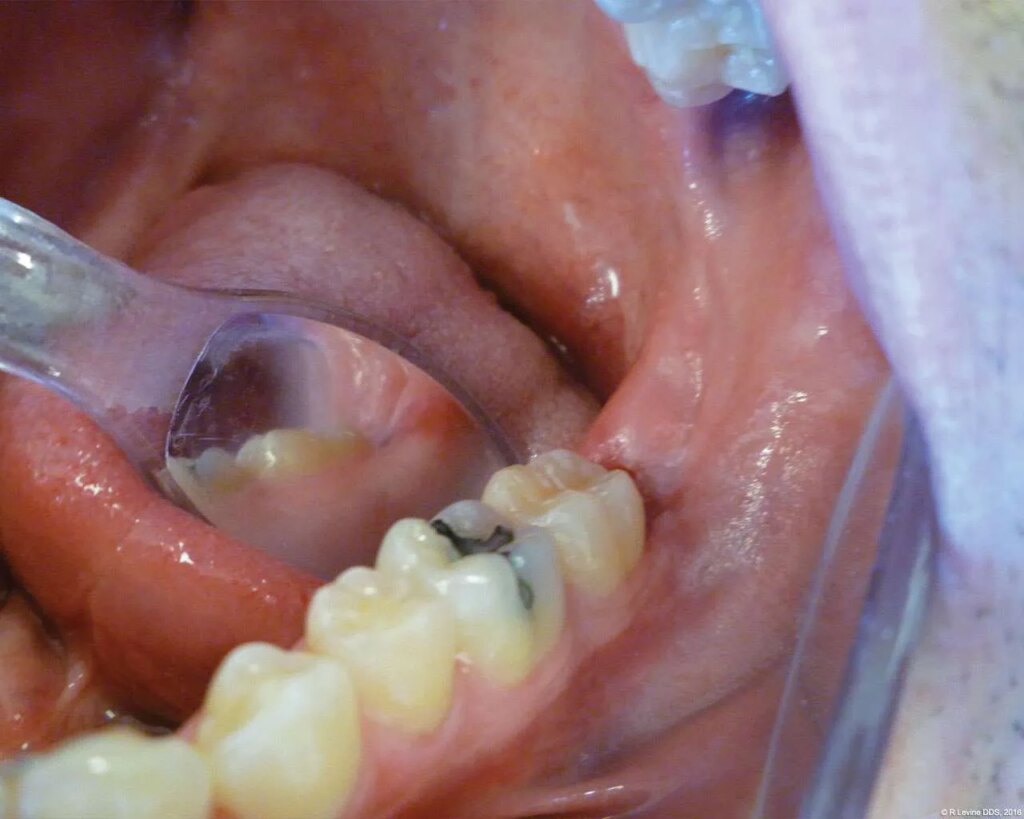

The patient presented with a raised, inflamed, painful operculum distal to the left mandibular second molar (Figure 3). The lesion was red, edematous, and bled easily. A periodontal pocket on the distal of the second molar was > 6 mm deep. There was no evidence of abscess.

- After the initial pass with the laser, the inflamed gingiva bled slightly and the surgeon defocused the beam by increasing the nozzle-to-tissue distance to quickly obtain hemostasis (Figure 6). Note the excellent visualization and the clear operatory field.